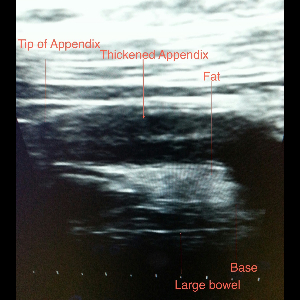

Appendicitis

Appendicitis

Appendicitis

Appendicitis